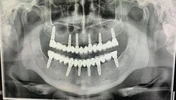

Implant tedavisi